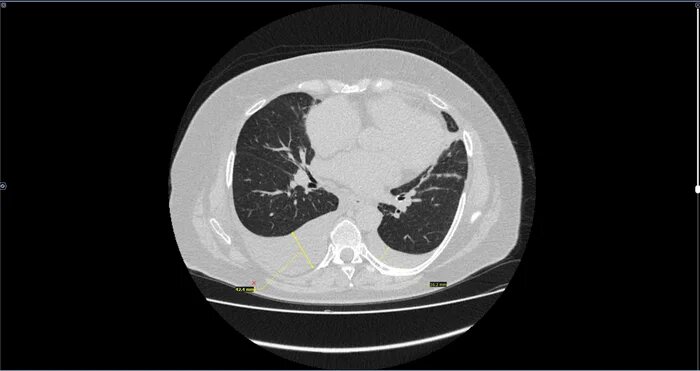

КТ-Гидроторакс⁠⁠

Двустороннее ассиметричное скопление жидкости плотностью +10-20 HU,с максимальной толщиной выпота справа -42мм,слева-16мм(ориентировочный объем жидкости справа-530мл,слева-157мл).

Заключение: Двусторонний гидроторакс, средний по объему-справа, малый-слева.